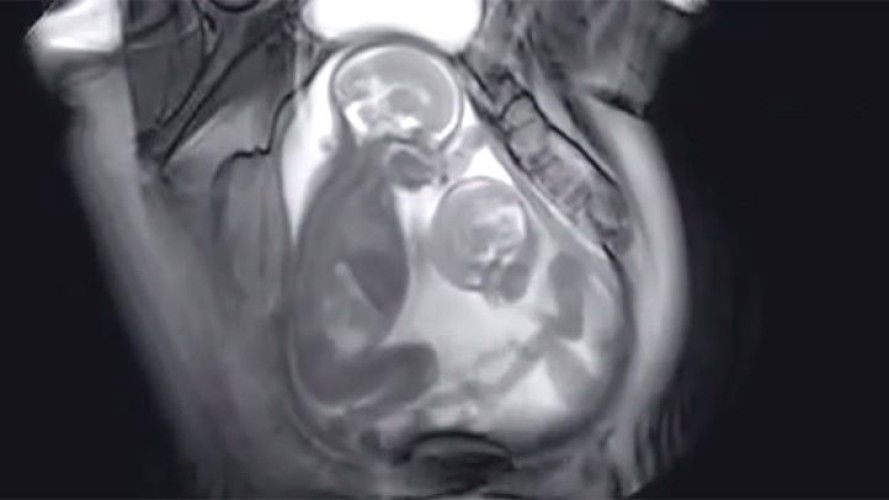

paling kerap waktu pagi dan malam...nak2 kembar sgt2 terasa dan 2 2 active